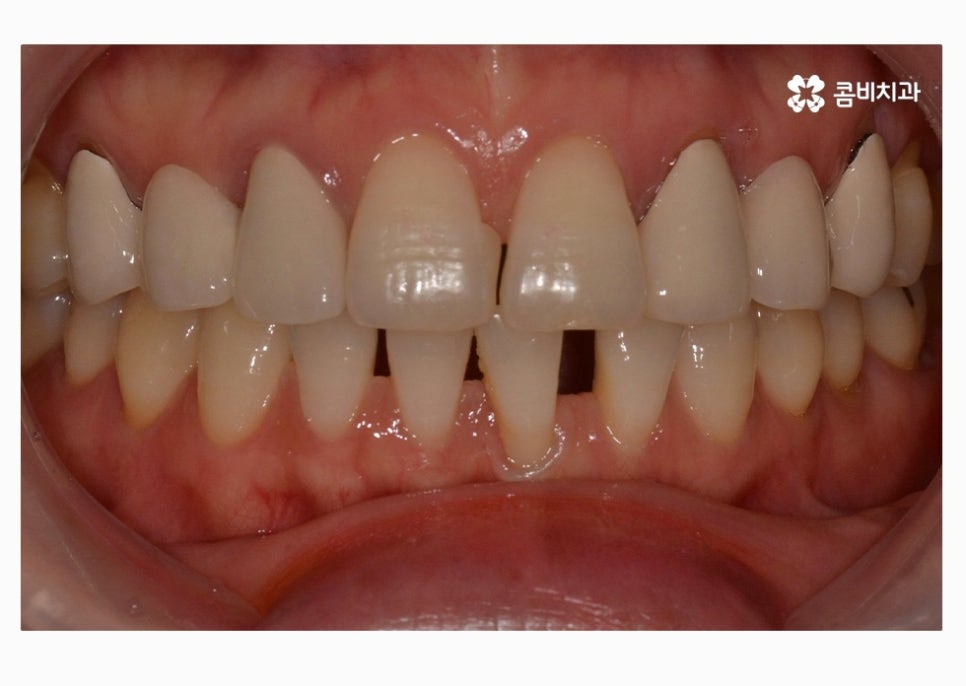

오늘 보실 30대임플란트 환자분의 사례는

윗니 2개를 충치로 인해 잃게 되어 임플란트를 하게 되었으며

아랫니가 벌어져 있고 치열이 고르지 못해서

치아 관리에 어려움을 느꼈기 때문에 치아 건강과

심미적인 치열을 위해서 치아교정도 함께 진행된 사례라고 할 수 있어요.

위에 표시된 치아는 이미 발치가 된 상태에서 임시치아를

부착하고 생활을 하셨던 환자이며 고르지 못한 치열을

개선하고 임시치아를 부착한 치아에 임플란트를 식립한 사례라고 할 수 있어요.

자세히 보시면 임시치아라는 것을 알 수 있고 엑스레이

사진을 보면 더 자세히 알 수 있습니다.